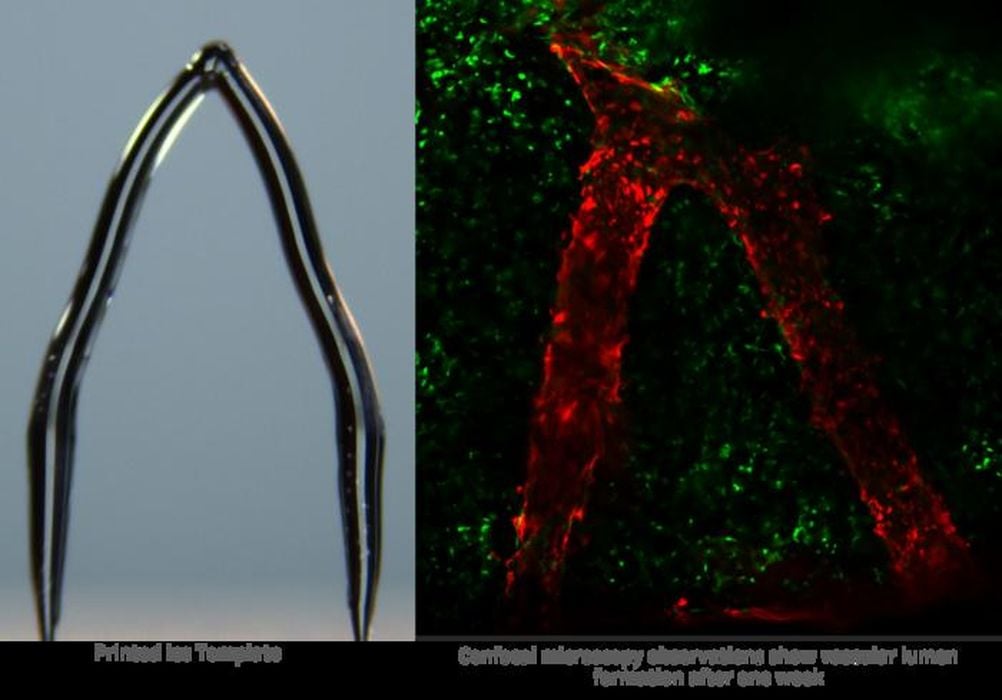

Ice 3D Printing: A Cool New Approach to Developing Artificial Blood Vessels for Organ Bioprinting

Researchers have developed a unique way to use “ice 3D printing” to help produce artificial human organs.

Researchers Develop Ice 3D Printer

There’s now a way to 3D print ice.